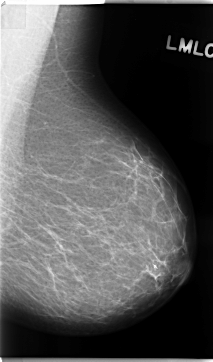

C_0131_1.LEFT_MLO

LEFT_MLO LINES 4696 PIXELS_PER_LINE 2760 BITS_PER_PIXEL 12 RESOLUTION 50 NON_OVERLAY